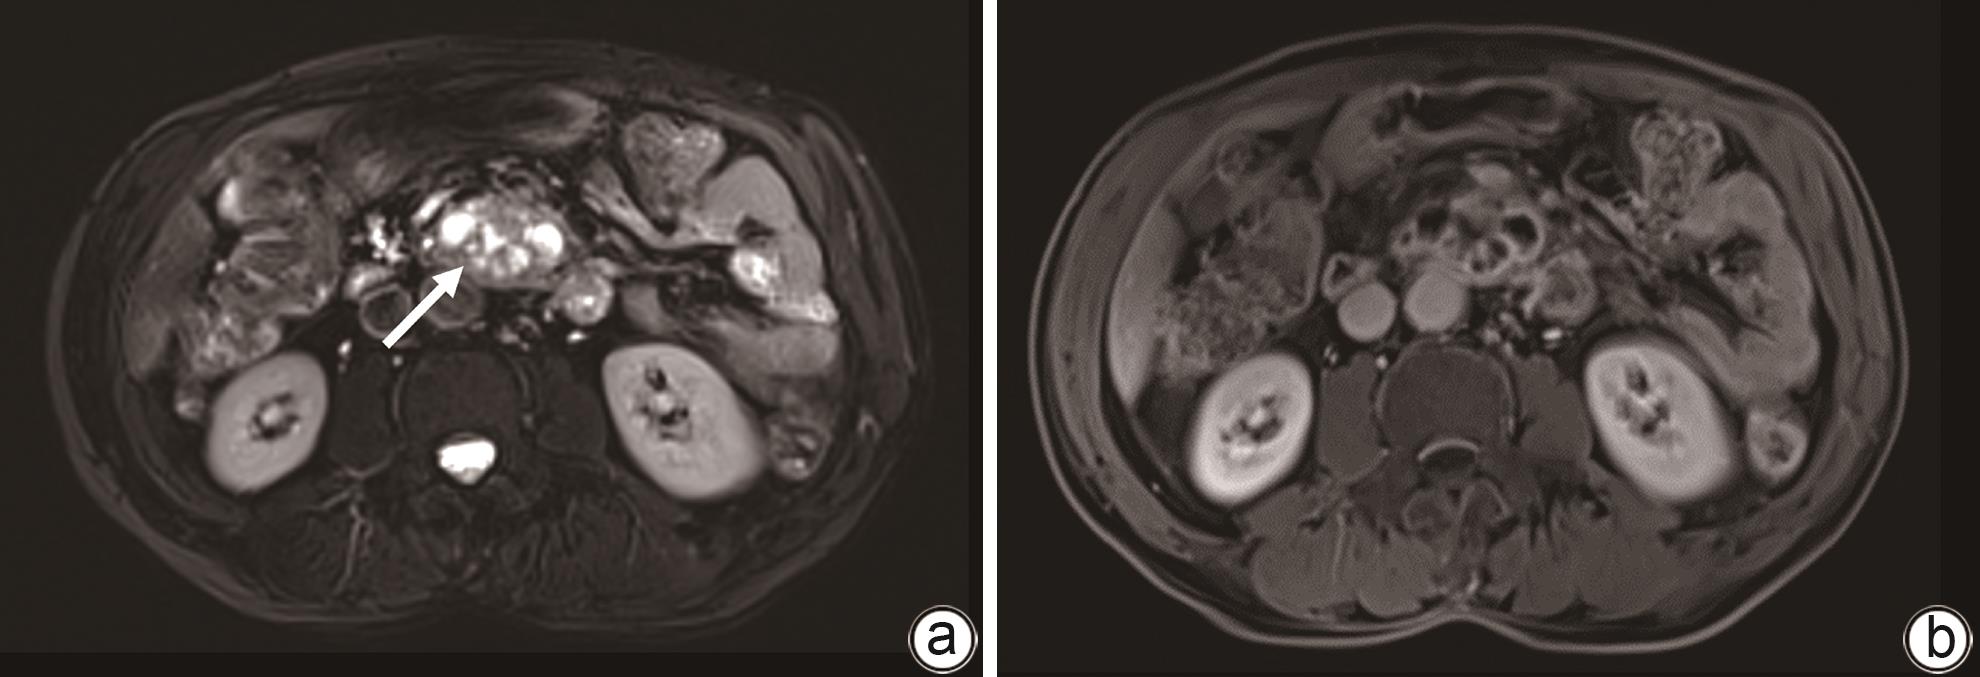

Clinical effect of Foley catheter through sinus tract in treatment of complex pancreatic fistula with massive venous hemorrhage after pancreaticoduodenectomy: A case report

At present, vascular intervention and surgery are the main methods for the treatment of pancreatic fistula with bleeding after pancreaticoduodenectomy, but these treatment methods have certain drawbacks, such as the complications of pancreatic fistula, bleeding, and abdominal infection after surgical treatment, and interventional treatment sometimes fails to identify the bleeding site. This article reports a case of complex pancreatic fistula with massive venous hemorrhage after pancreaticoduodenectomy treated with Foley catheter balloon compression through the drainage tube sinus. Bleeding was arrested and gastrointestinal fistula was cured after catheter balloon compression and effective drainage, with no complications such as pancreatic pseudocyst, intestinal ischemia, and portal hypertension.